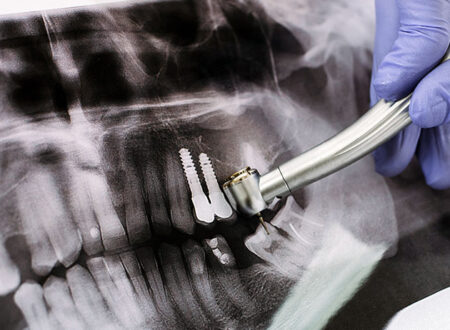

Sinüs Lift

Sinüs Lift Üst çenede arka bölgede yer alan küçük azı ve büyük azı dişlerinin erken yaşta kaybedilmeleri sonrası maksiller sinüs